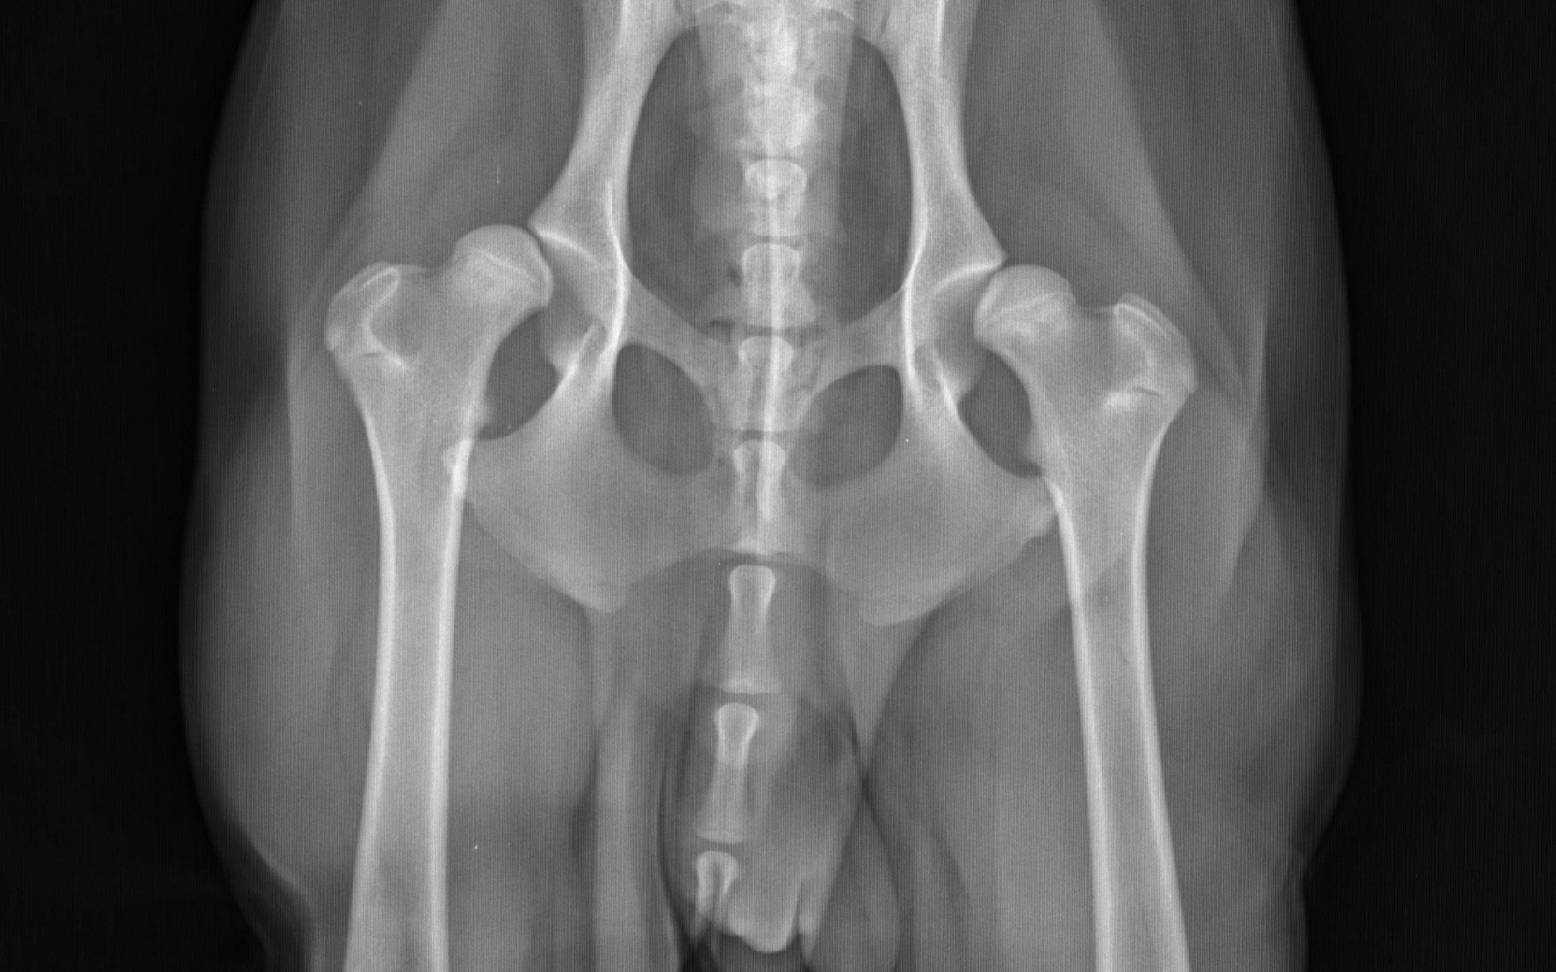

Dein/e Tierärzt:in erhält anhand deines Vorberichts und einer eingehenden orthopädischen Untersuchung schon deutliche Hinweise auf das Vorliegen einer HD. Durch verschiedene passive Mobilitätstests kann er/sie Schmerzhaftigkeit, Instabilität oder Bewegungseinschränkungen des Hüftgelenks feststellen. Der Verdacht einer HD kann allerdings nur mit Hilfe von Röntgenbildern eindeutig bestätigt werden. Um den exakten Grad der HD zu bestimmen, muss dein Hund ausgewachsen sein, da die Entwicklung des Hüftgelenks erst mit dem Ende des Knochenwachstums abgeschlossen ist.

Die von den verschiedenen Zuchtverbänden geforderten Röntgenaufnahmen dürfen daher erst ab einem bestimmten Mindestalter und nur nach speziellen Lagerungs- und Belichtungskriterien durchgeführt werden. Des Weiteren muss dein Hund für die Anfertigung offizieller Aufnahmen in Narkose gelegt werden. Werden die Aufnahmen nur zur Abklärung einer Lahmheit benötigt, ist dies zwar nicht vorgeschrieben, aber häufig auch notwendig und sinnvoll, um auswertbare Röntgenbilder zu erhalten.